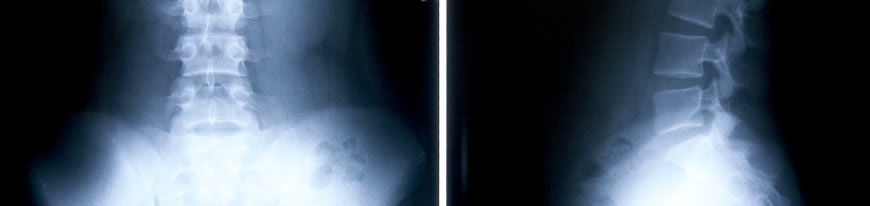

- Complete spinal examination

- Lateral spine view